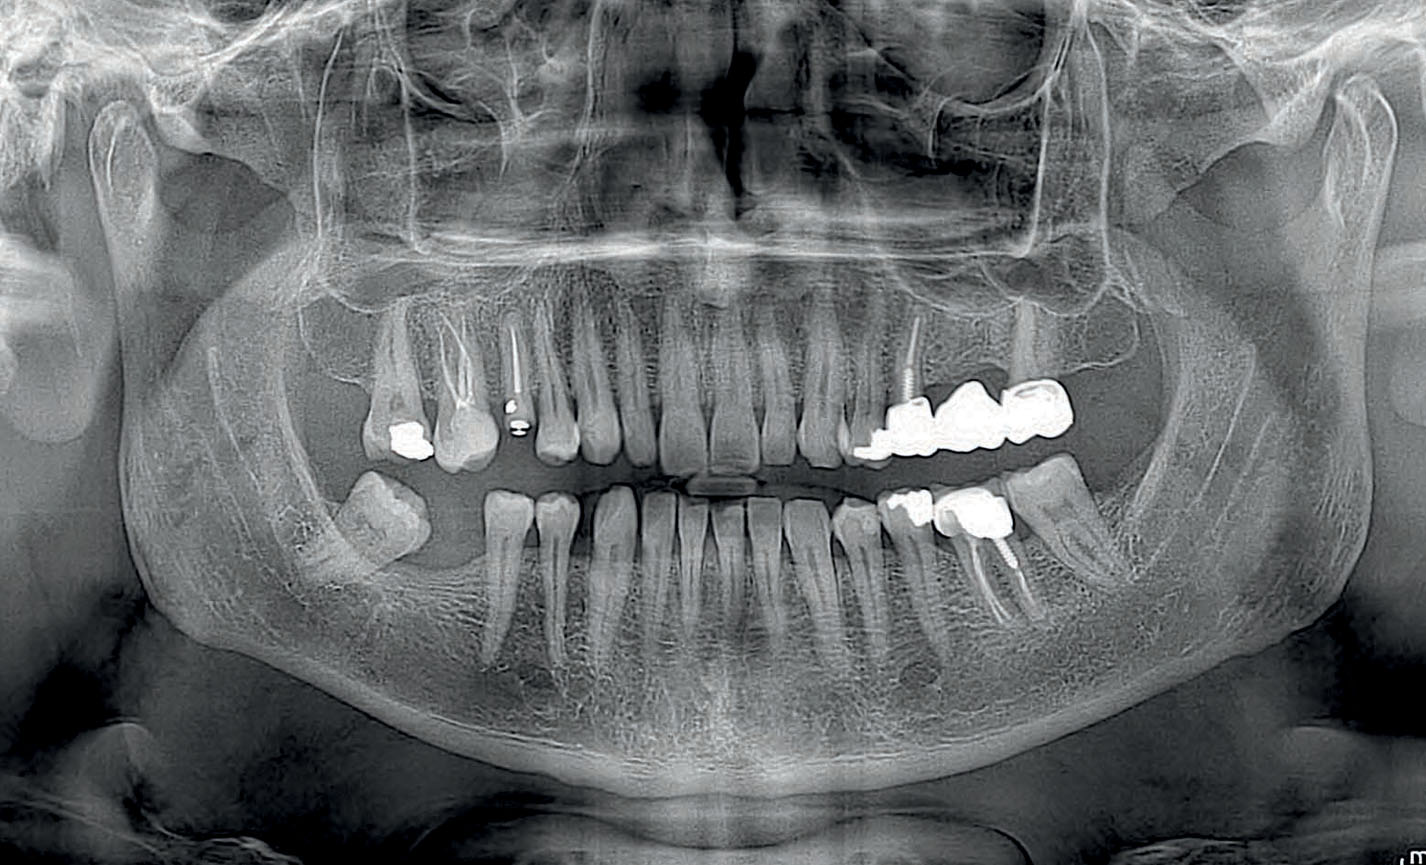

Panoráma röntgen           - azonnal beutaló nélkül -

Rendelőnkben egy minden igényt kielégítő digitális Myray Hyperion X5 panoráma röntgen áll rendelkezésre.

Kimagaslóan jó képminőség, modern, precíz működés, alacsony sugárdózis

panoráma röntgen felvétel